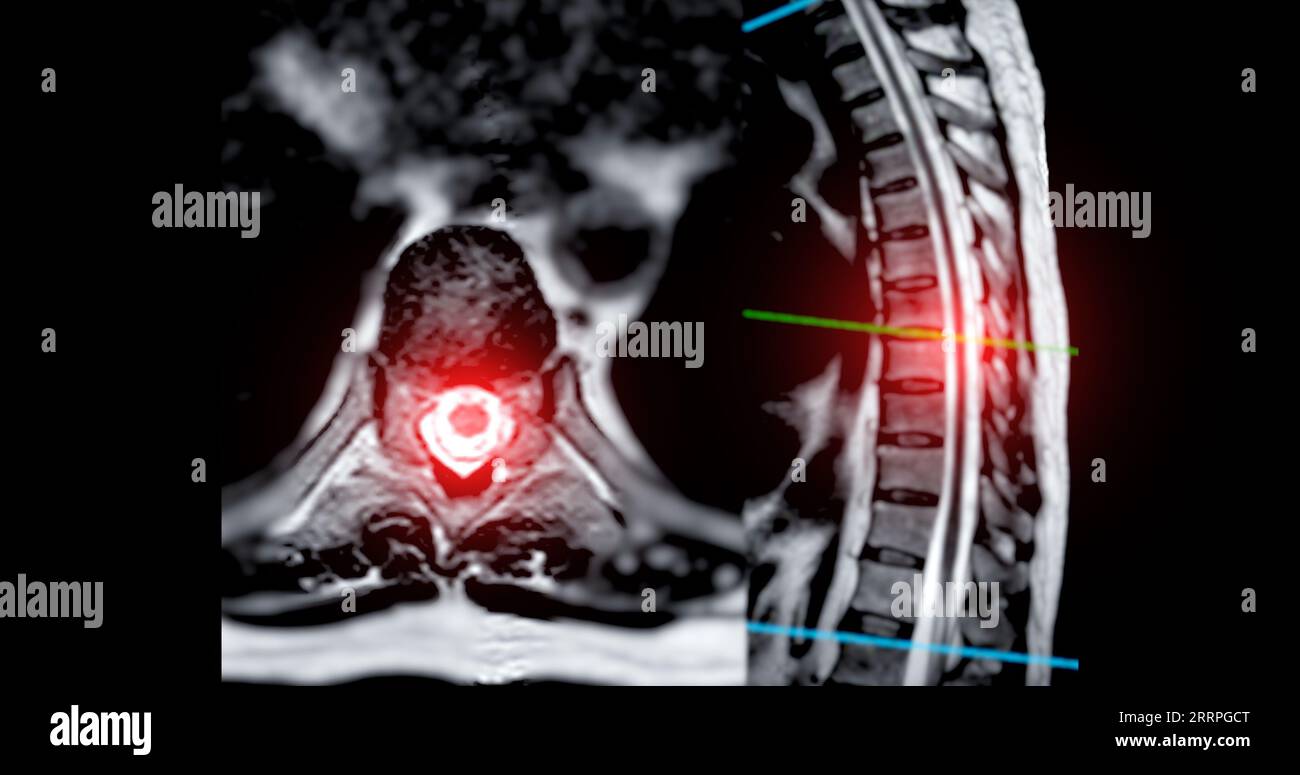

MRI TL spine or Thoracosacral spine Axial and sagittal T2 technique Sacral Spinal Cord Compression The spinal cord is a thick bundle of nerves that runs down your spinal column. spinal cord compression can occur anywhere from your neck (cervical spine) down to your lower back (very top of lumbar spine). Common causes include injury and conditions that put pressure on the spinal cord. spinal cord compression can result from a myriad of. Sacral Spinal Cord Compression.

MRI TL Spine or Thoracosacral Spine Axial and Sagittal T2 Technique Sacral Spinal Cord Compression spinal cord compression can result from a myriad of both atraumatic and traumatic causes. The spinal cord is a thick bundle of nerves that runs down your spinal column. the spinal cord may be compressed by bone, blood (hematomas), pus (abscesses), tumors (cancerous or not), or a ruptured or. spinal cord compression—also called cervical spondylotic myelopathy (csm)—. Sacral Spinal Cord Compression.